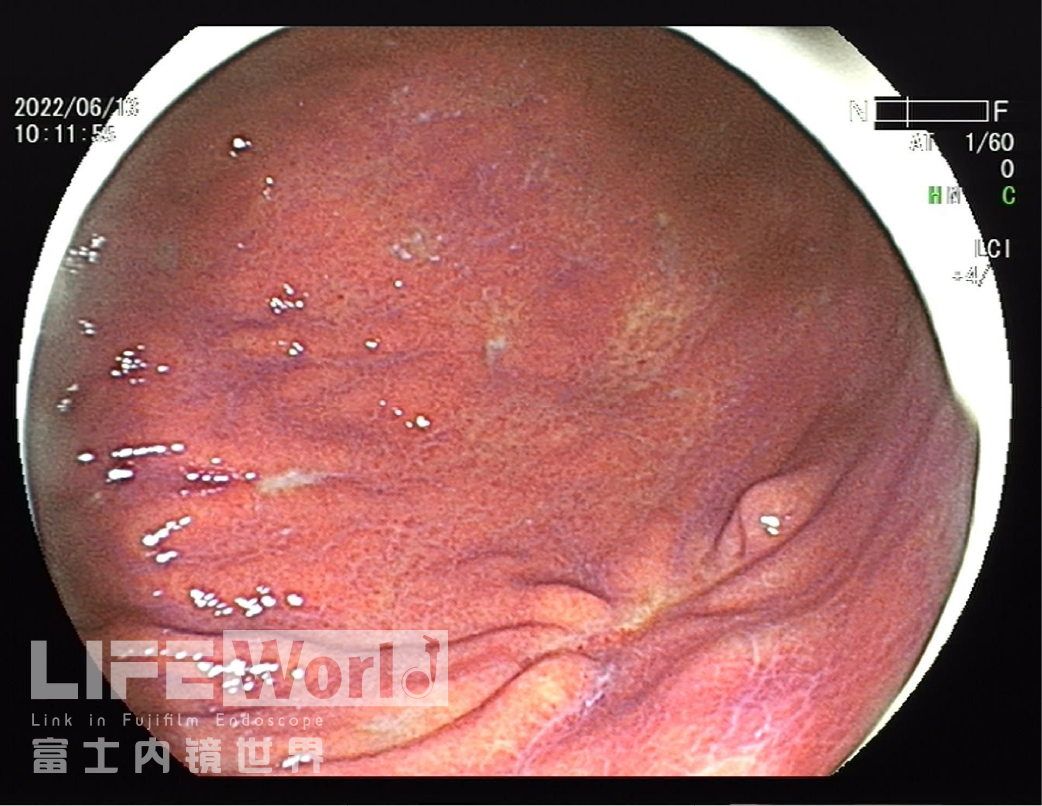

白光观察:胃体下段大弯侧可见一处中央凹陷的病变,色红,范围约1.2×0.6cm,周围黏膜集中、中断。

LCI模式:病变为橙黄色,周围黏膜呈紫红色。